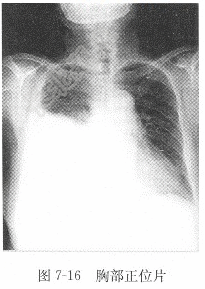

试题详情单项选择题女性,28岁,胸痛半月,X线图像见图7-16,X线诊断为( )。A、右侧胸腔积液B、右下肺结核C、右下肺炎D、右下肺癌正确答案:关注下方微信公众号,搜题查看答案热门试题血hCG检测心脏扩大男性,60岁,摔伤20min,下肢X线图血清氨基转移酶房性期前收缩检查血清碱性磷酸酶(ALP)血清钠参考值脾外伤血清总胆红素(STB)和结合胆红素(CB血清铁测定铁蛋白(SF)正常心电图检查男性,44岁,进行性咽下困难2周,食管造正常胸部正位片粪便潜血试验(occult blood 正常腹部平片典型浸润型肺结核急性硬膜下血肿胃癌肢体骨折正、侧位片